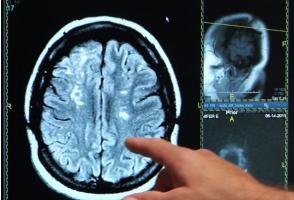

MALADIE CORONARIENNE : Précoce, elle prépare le lit de la démence

Actualité publiée le 31/12/2020COVID-19 et AVC : Comment le virus nous prend la tête

Actualité publiée le 20/12/2020